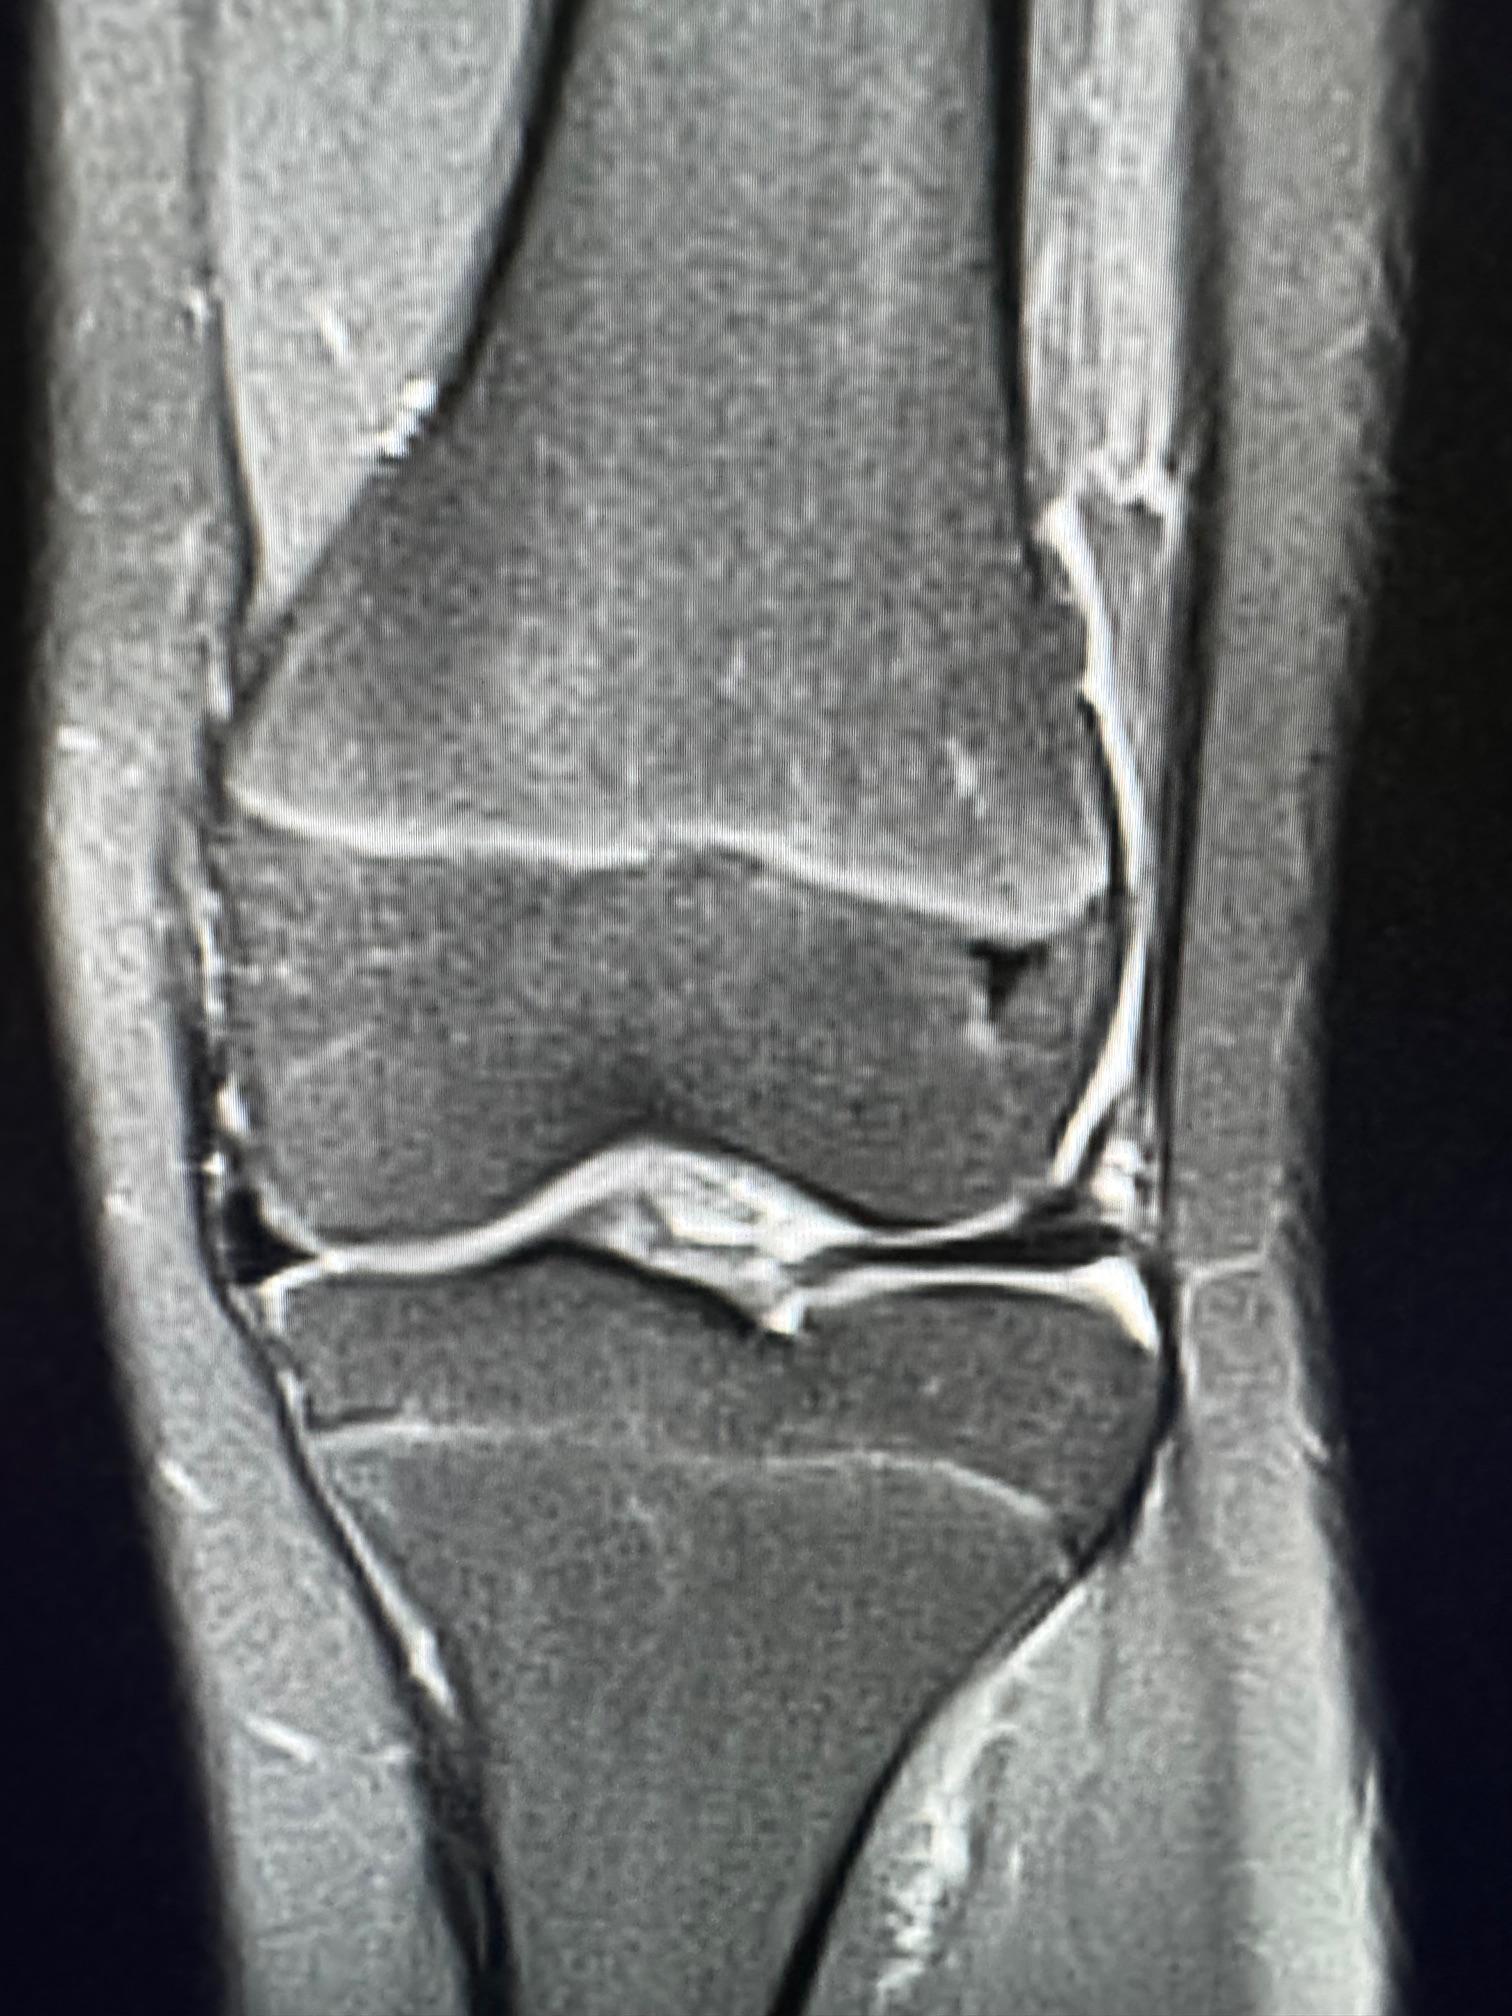

![]()